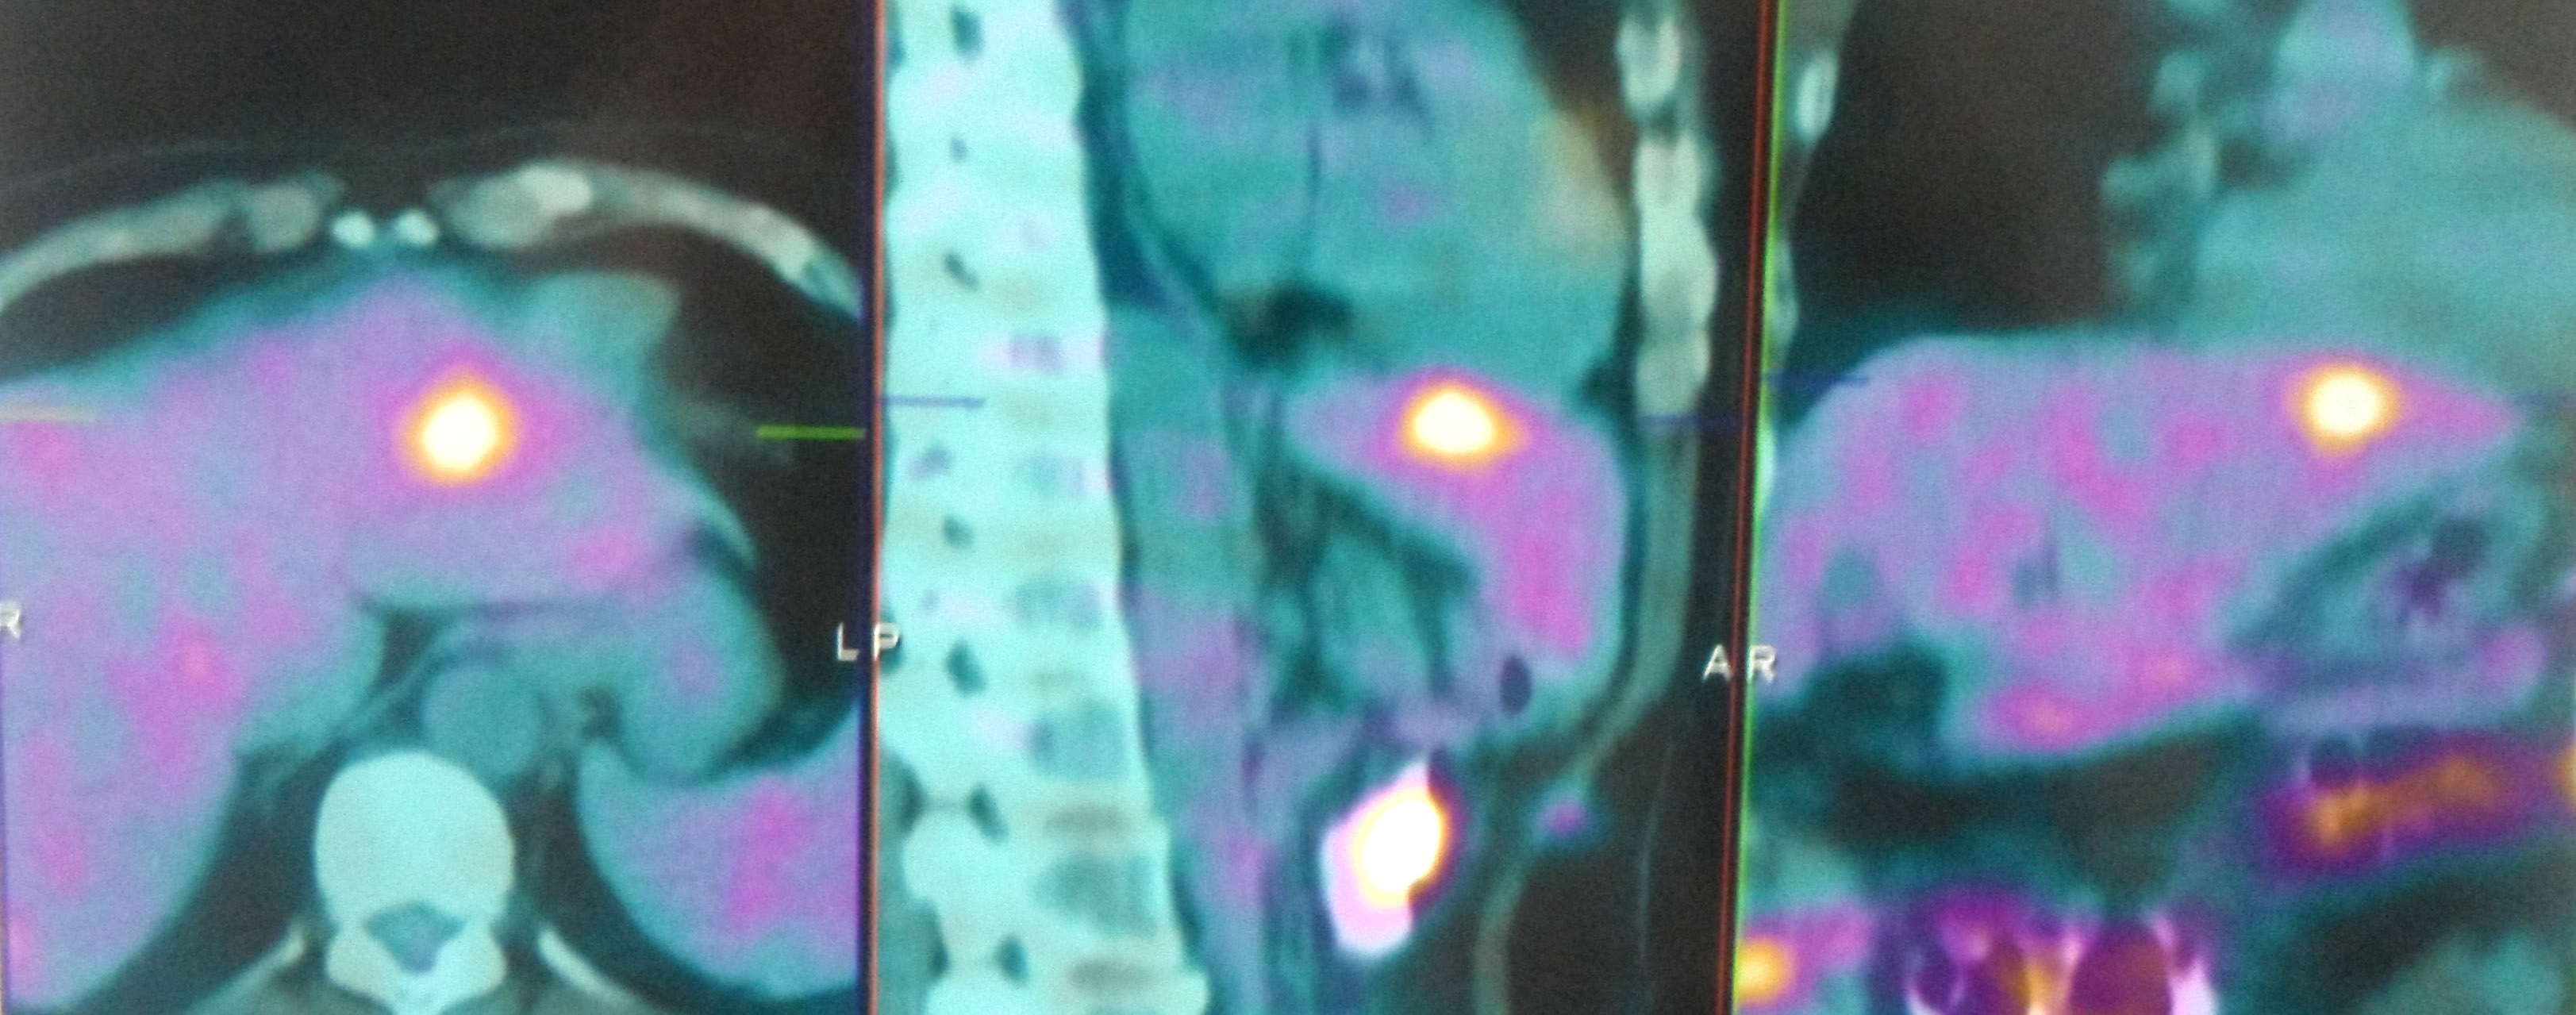

A PET scan showed:

- Two hypermetabolic metastatic nodules in the liver.

- No abnormal hypermetabolic foci or metastases elsewhere.